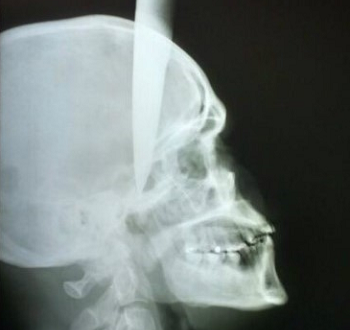

Um homem identificado como José de Ailton, de 35 anos, sofreu uma tentativa de homicídio em Garanhuns, no Agreste do Estado e foi levado para o Hospital da Restauração, na área central do Recife, com uma faca cravada na cabeça. De acordo com a Polícia Militar, o homem foi esfaqueado após uma discussão enquanto bebia com o suspeito do crime, na noite de domingo (09), na Zona Rural da cidade.

Segundo informações, inicialmente, entre 21h e 22h do domingo (09), o homem, que também estava com ferimentos no braço direito, e no tórax, foi socorrido para o Hospital Dom Moura, em Garanhuns. Por volta das 22h40, ele foi transferido para o Hospital da Restauração, onde passa por procedimento cirúrgico, na manhã desta segunda (10).